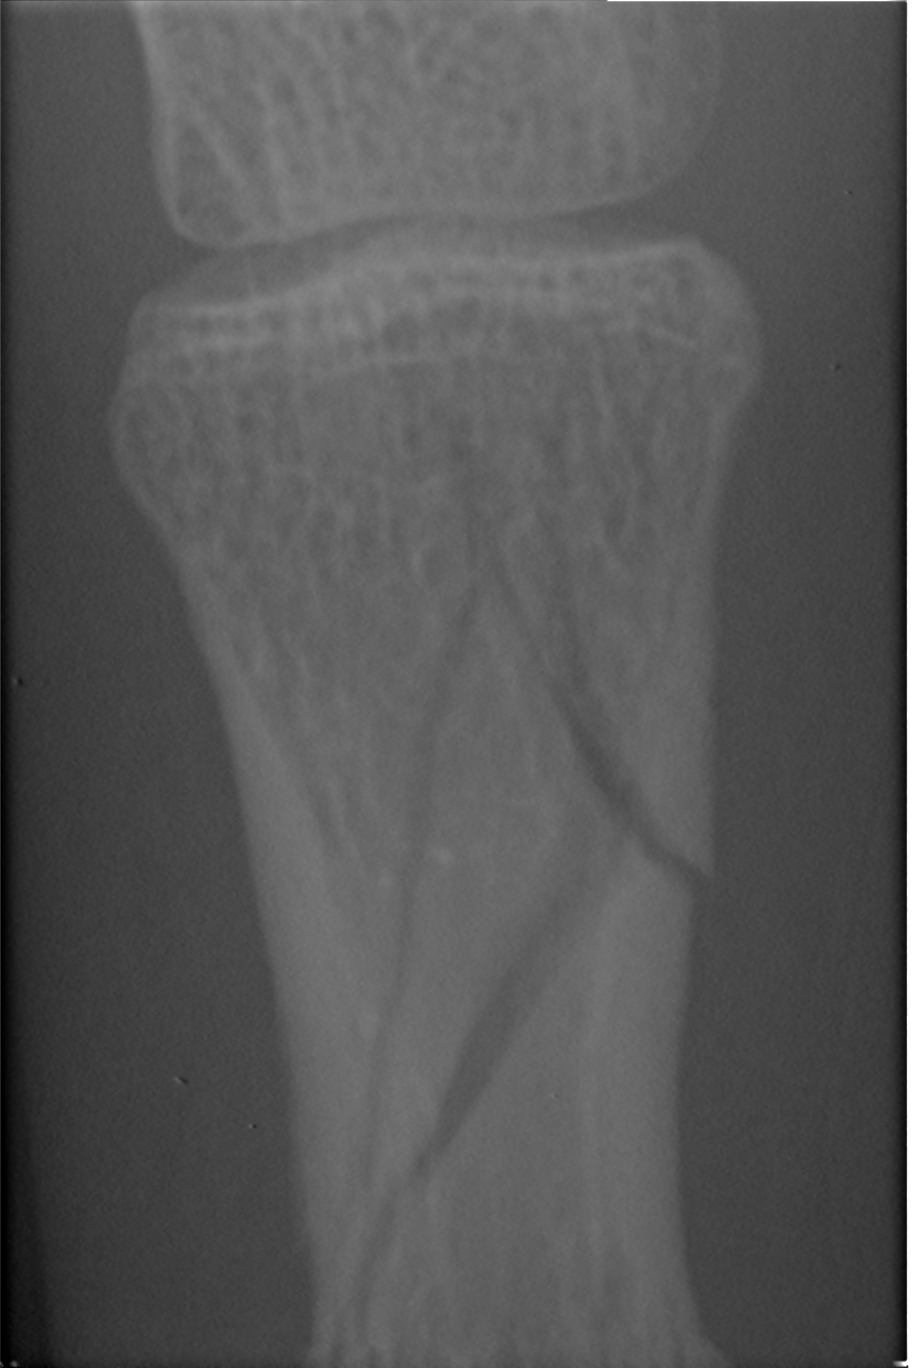

Broke the 2d phalanx of my 4th finger yesterday during a frontside... hit a iceball of the death due to poor grooming and icy slopes after warm days...did not see it (white out day)

here are the photos:

full plaster:

cuted: